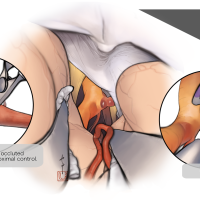

OPExPARK20220130コンテンツシリーズ